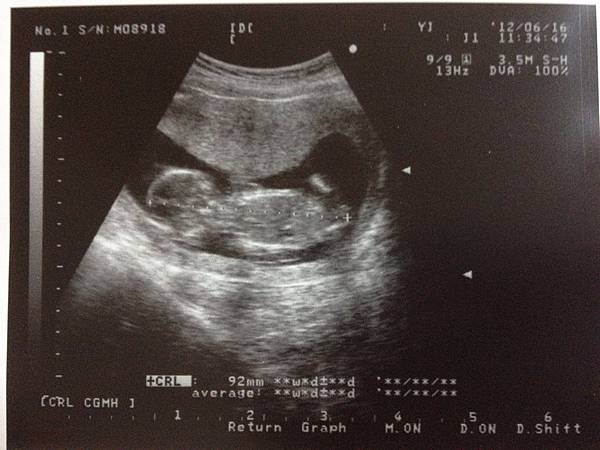

6/16又是產檢日啦!今天老公一樣一大早出門去排曾英智醫生的診號。

而這次是14w5d的產檢,原本就有在猜是不是這次會知道性別!

結果,曾醫生果然當場宣佈答案啦!

一開心聽心跳,然後看到腳開開的"紀念品"